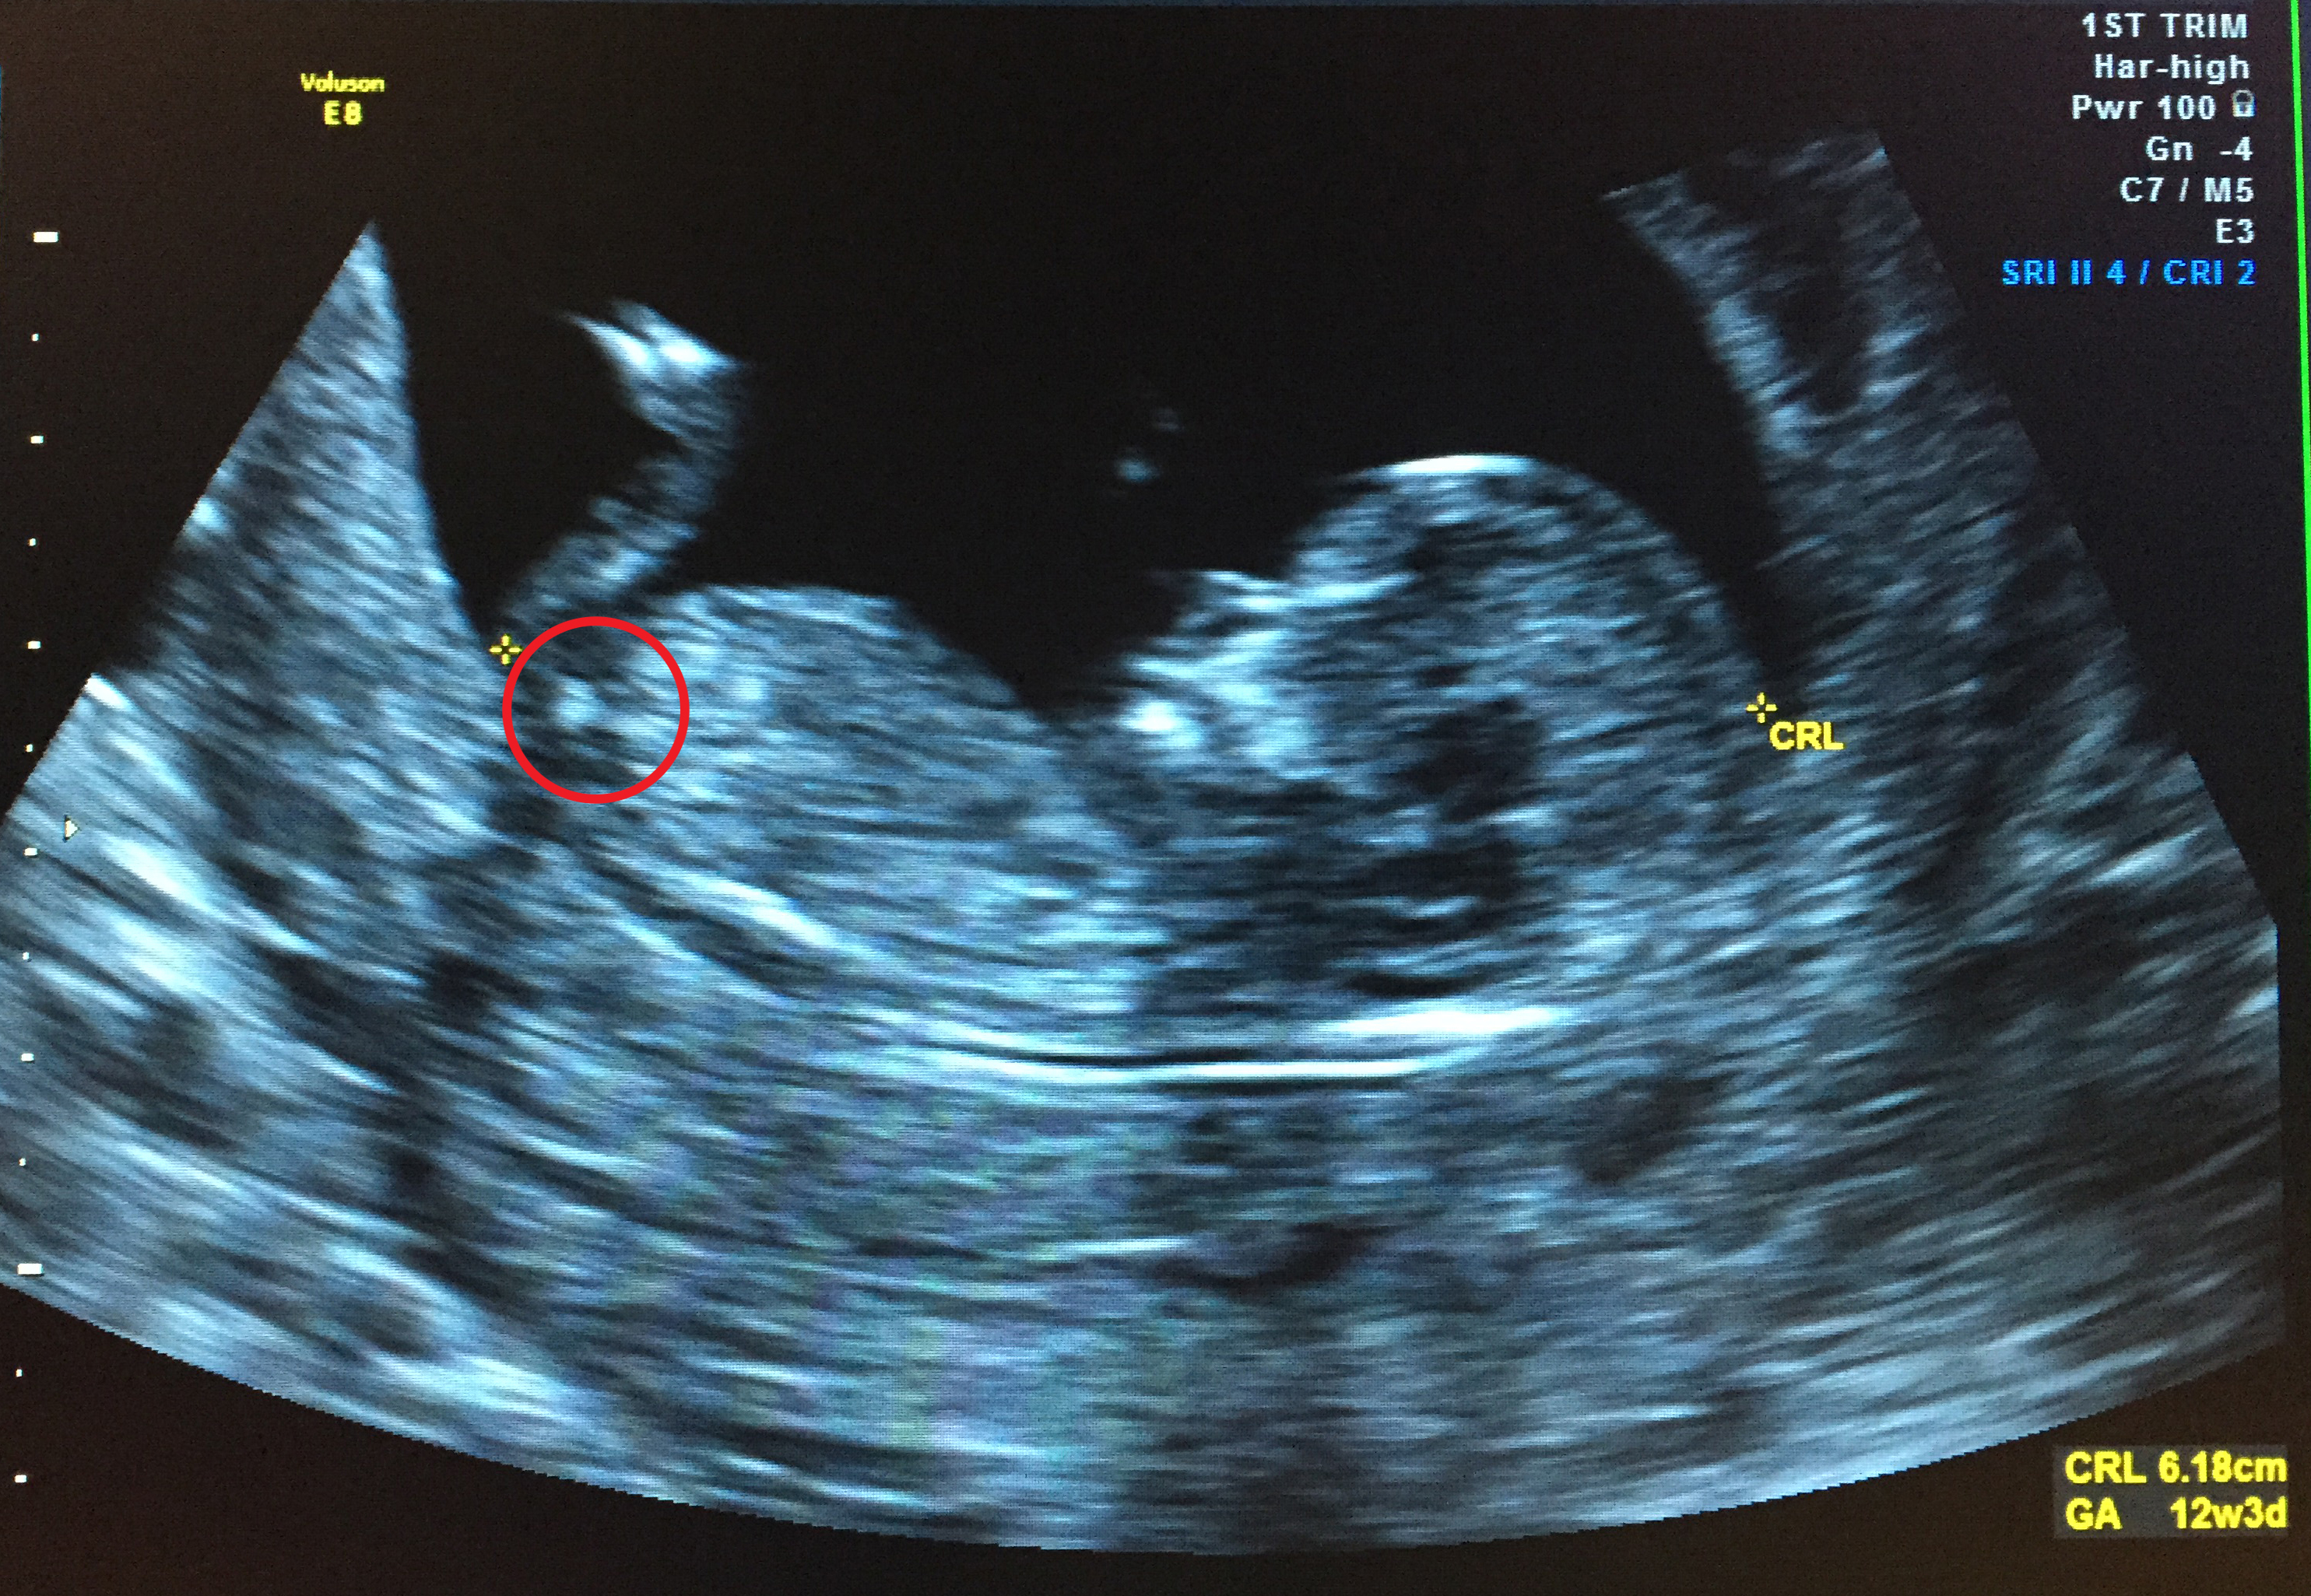

I had my NT scan today. I'm 12 weeks and 3 days pregnant. I'd love some guesses on the gender based on the nub and/or the skull. :)

I think there might be a girly nub there.

Thanks Claire! Can I just ask which bit looks like the nub to you? I'm so clueless about the nub theory and have circled what I thought was the nub, but other people have said that they can't see a nub, so I"m wondering if I'm looking at the wrong part?!

Yes, that is what I think is the nub.